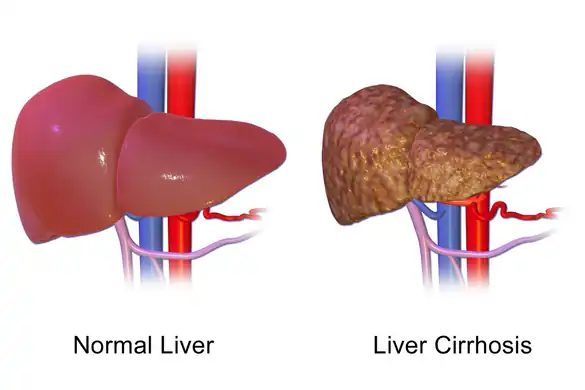

Liver disease

Albumin is synthesized in the liver, and low serum albumin can be indicative of liver failure or diseases such as cirrhosis and chronic hepatitis. If present, hypoalbuminemia is generally considered to be a sign of advanced hepatic cirrhosis, or irreversible damage to the liver.[3] Production of albumin can be 60–80% lower in advanced cirrhosis than in healthy liver, an effect amplified by dilution (salt and water retention), fluid shifts (following the accumulation of albumin in extracellular space and ascitic fluid), and even post-transcriptional changes to albumin itself.[8]